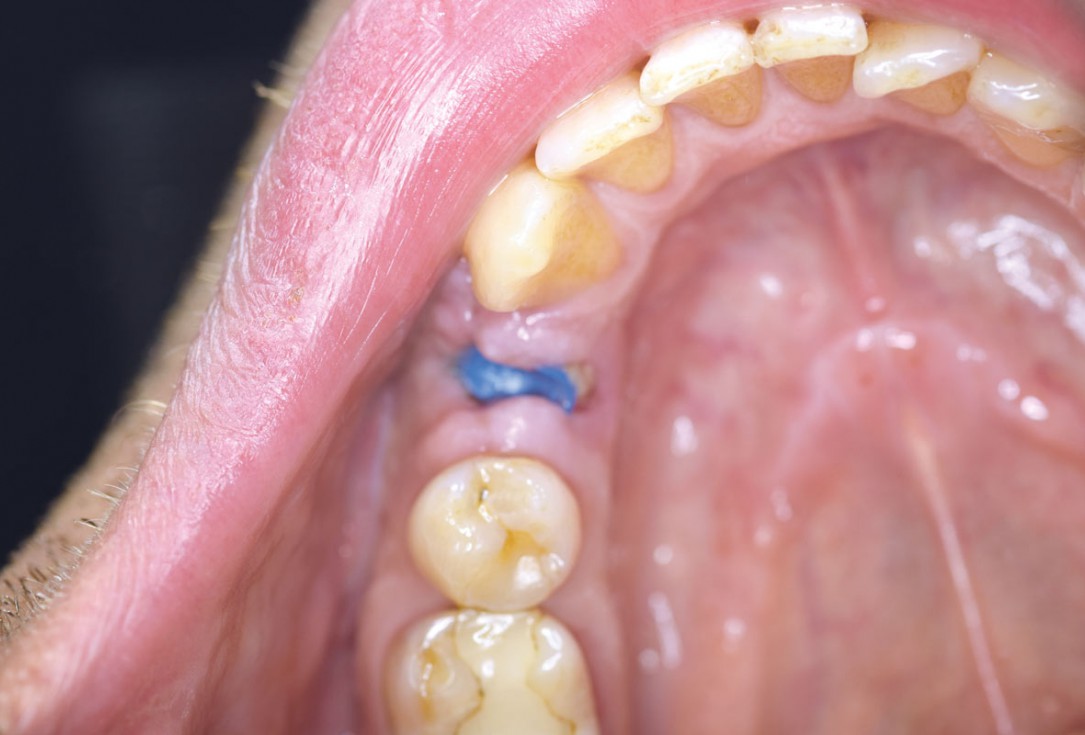

Posterior socket preservation using maxgraft® and permamem® - Dr. C. Landsberg